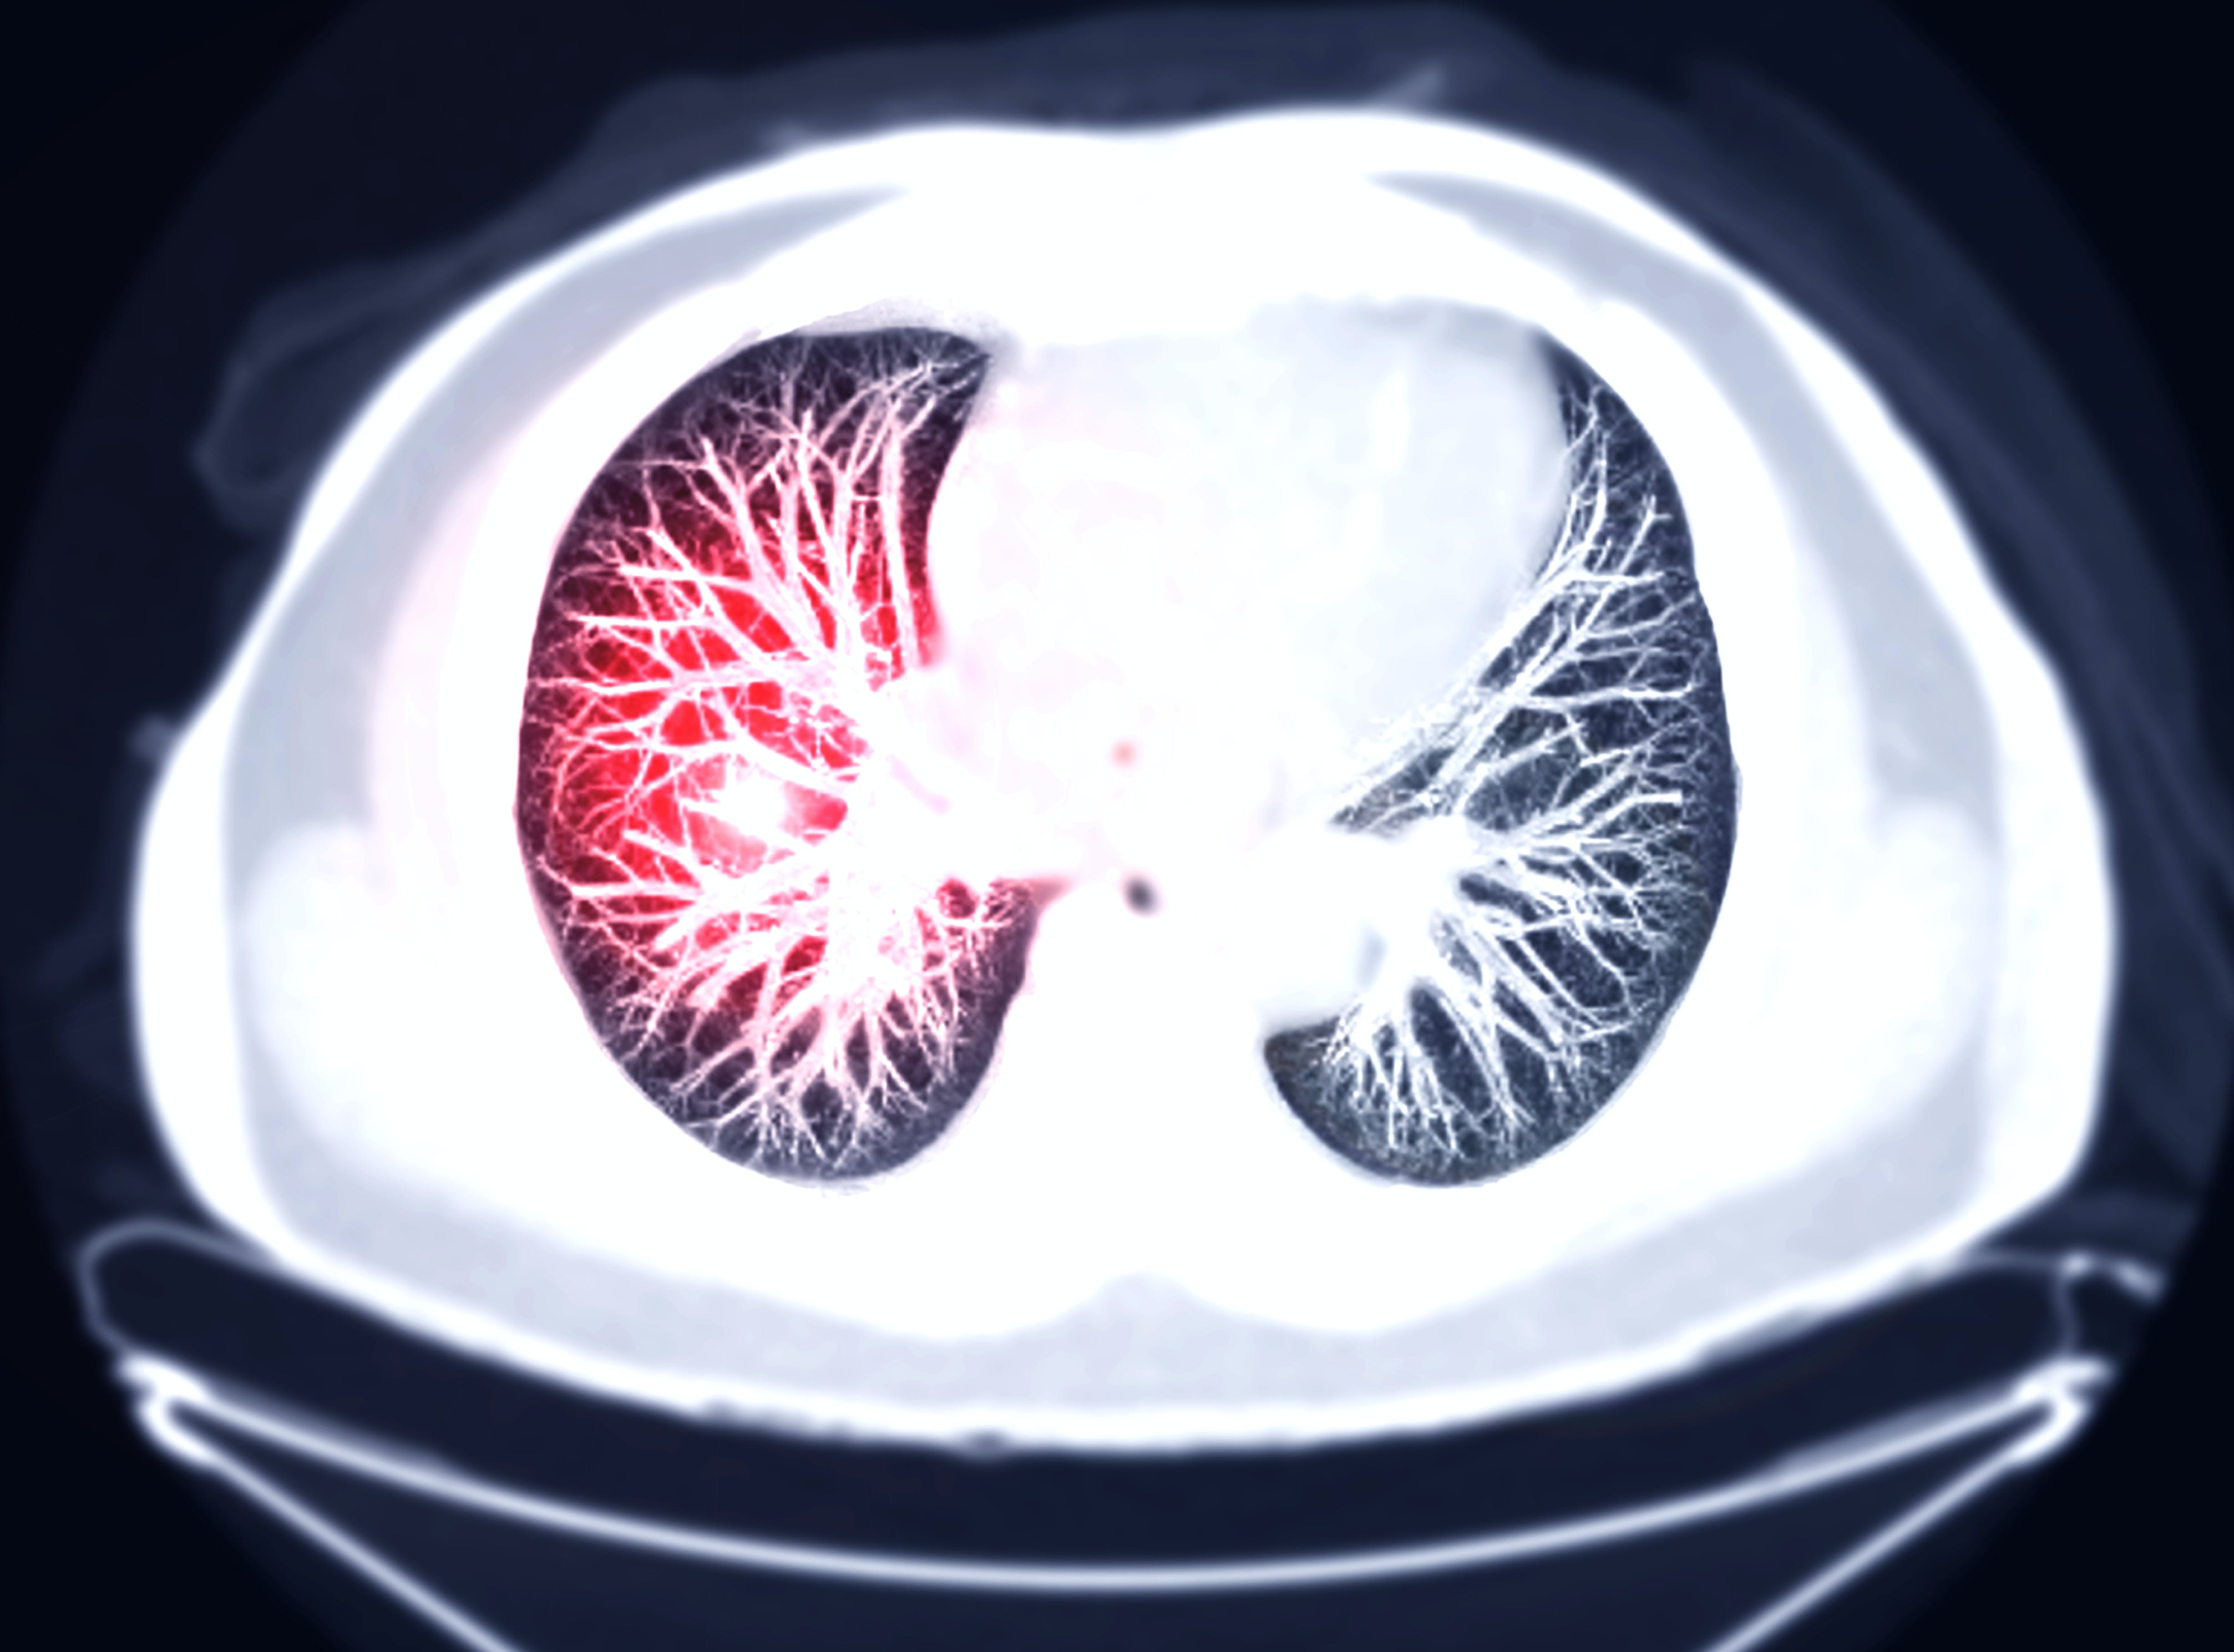

Diagnosing early-stage lung cancer with low-dose computed tomography (CT) screening drastically improves the survival rate of cancer patients over a 20-year period, according to a large-scale international study presented by Mount Sinai researchers at the annual meeting of the Radiological Society of North America.

The results show that patients diagnosed with lung cancer at an early stage via CT screening have a 20-year survival rate of 80 percent. The average five-year survival rate for all lung cancer patients is 18.6 percent because only 16 percent of lung cancers are diagnosed at an early stage. More than half of people with lung cancer die within one year of being diagnosed, making it the leading cause of cancer deaths. By the time symptoms appear, it is often too late.

The study tracked the 20-year survival rate of 1,285 patients who were screened in the International Early Lung Cancer Action Program (I-ELCAP) and who were later diagnosed with early-stage lung cancer. While the overall survival of the participants was 80 percent, the survival rate for the 139 participants with nonsolid cancerous lung nodules and the 155 participants with nodules that had a partly solid consistency was 100 percent. For the 991 participants with solid nodules, the survival rate was 73 percent. For participants with Stage 1A cancers that measured 10 mm or less, the 20-year survival rate was 92 percent.